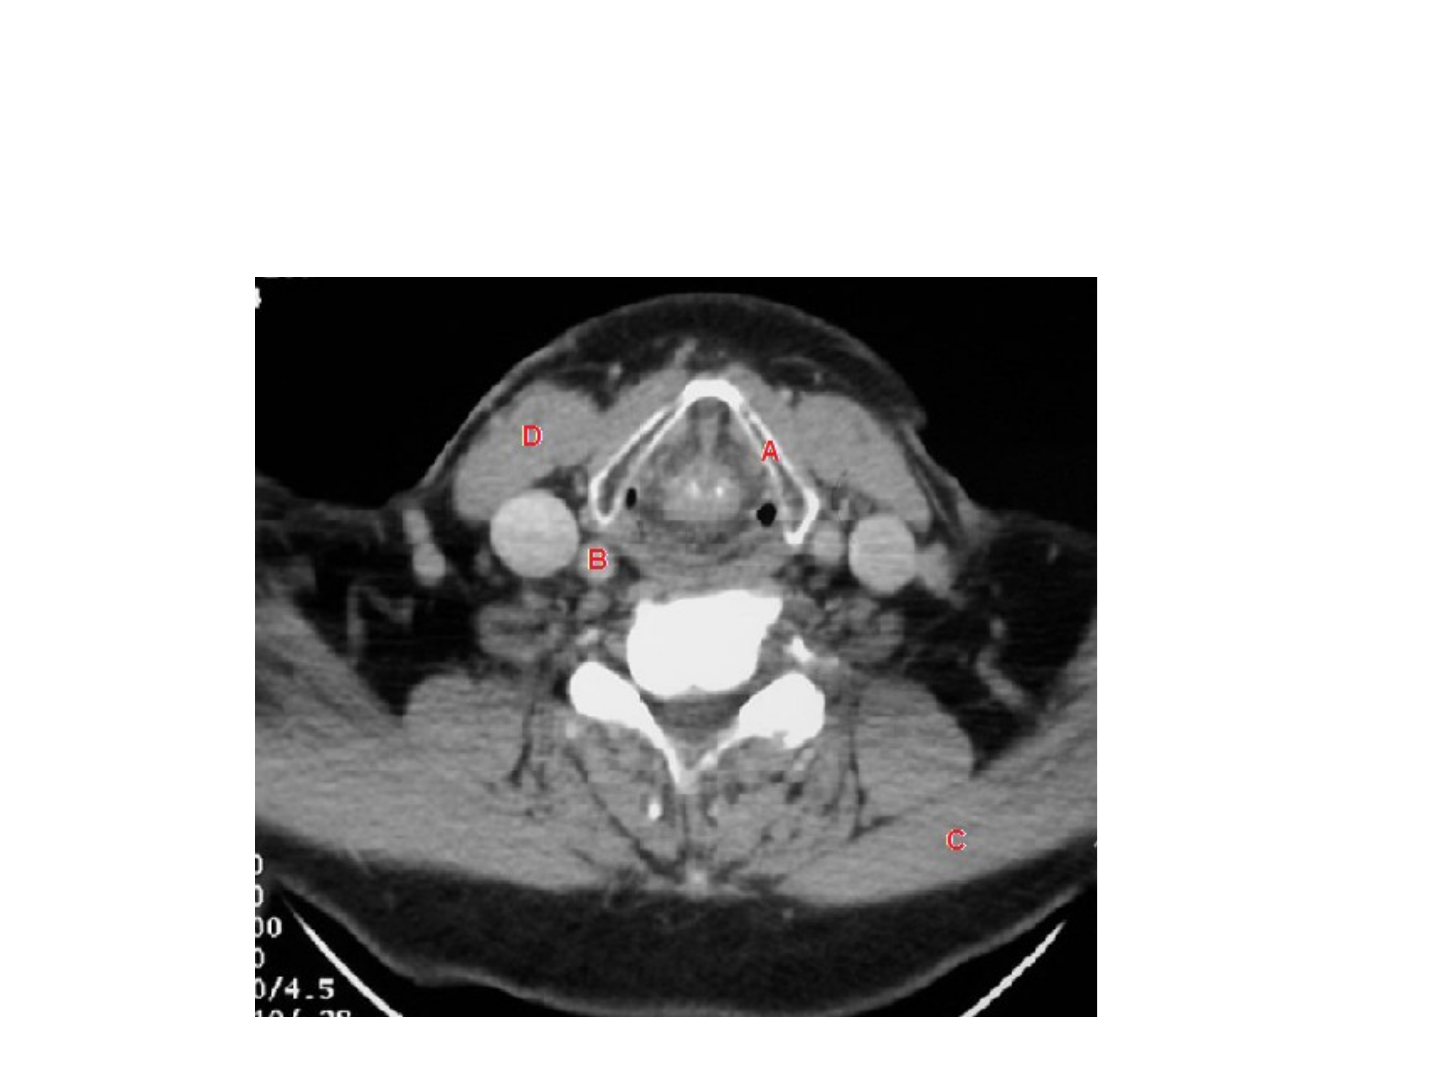

A: Cartíl

ago tir

o

ides.

B: Art

eria Car

ótida Pri

mitiv

a der

echa.

C: Músculo T

r

apecio iz

q

uier

do.

D: Músculo E

CM der

echo.